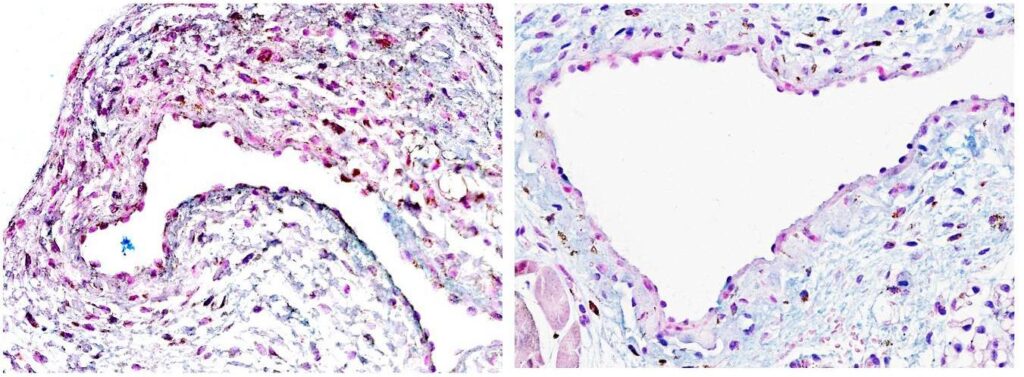

Células-tronco podem oferecer uma nova esperança para o tratamento da doença renal em estágio terminal

ROCHESTER, Minnesota — Mais de 4 milhões de pessoas em todo o mundo têm doença renal em estágio terminal que requer hemodiálise, um tratamento no qual uma máquina filtra as impurezas do sangue. A hemodiálise é uma etapa que antecede o transplante de rim. Para se preparar para isso, os pacientes geralmente passam por uma cirurgia para conectar […]